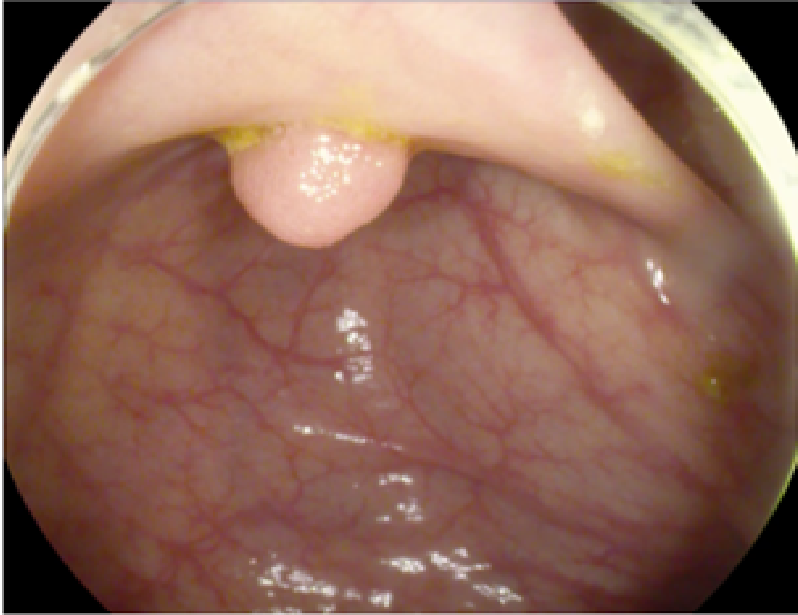

The study used a publicly available dataset of polyp-frames obtained from the ETIS-Larib database [34], containing 196 polyp images. These images were obtained from 34 different colonoscopy videos of 44 different polyps with various appearances and sizes, having a resolution of pixels. The ground truth of polyp areas for polyp datasets is determined by expert video endoscopists. A CNN model trained with such a small amount of data is likely to be meaningless and unstable, so data augmentation was performed on the polyp dataset. Data augmentation had to be performed on the colonoscopy images by considering vivid variations. Otherwise over-fitting would have occurred. In a colonoscopy imagery, polyps exhibits large variations in location, color, and scale. Moreover, variations in brightness and definition also occur due varrying the view-point of the camera. Therefore, in addition to photometric distortions and geometric distortions, we also have considered zooming, shearing, and altering brightness as strategies for data augmentation.

For photometric distortions, we controlled brightness and contrast as an enhancement, while blurring by adding noise with a standard deviation of 1.0. Similarly, for geometric distortions, clock-wise rotation of the polyp images with angles of , , and were performed. Zoom-in and zoom-out with zooming parameters such as 30.00% and 10.00% were performed to obtain different scales of polyp images. Lastly, shearing for both the x-axis and the y-axis was performed to shear the images from left to right and top to bottom, respectively. Fig. 4 shows photometric and geometric forms of image augmentation. In this way, we augmented the data set of the ETIS-Larib database from 196 polyp images to 2,156 images, which is more suitable for training the proposed deep CNN model.

The results shown in Fig. 6 are generated using the proposed deep CNN model on the augmented data set. It can be observed that the proposed model shows better polyp detection performance. As illustrated in Fig. 6, polyps within a frame can be identified at multiple positions, and as noted above in this case, the TP for detection is considered to be 1. The proposed deep CNN model performed better than other benchmark results in terms of the performance metrics listed above, as shown in Table. 2 and Fig. 6.